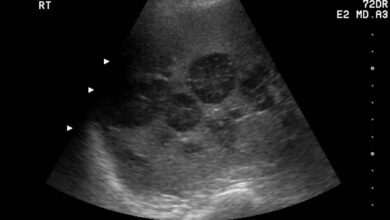

Рентген диагностика Рентген суставов является одним из основных методов визуализации для выявления артрита. Этот метод позволяет врачам получить детальные изображения…